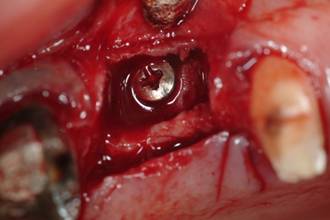

The graft was press-fit into the defect and a screw was inserted for internal fixation to increase stability (Fig. 6).

Figure 6

Graft stabilized with screw.

Int J Med Sci Image